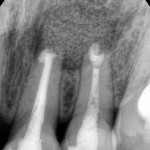

2013-07-26 PA 수술 후

치근단 수술 후 찍은 작은 사진입니다. 치아 뿌리 밑에 있던 염증조직을 긁어내고 뼈이식이 잘 되었음을 확인할 수 있습니다.

2013-11-16 PA 수술 후ck

4개월 후 check 사진입니다. 중절치와 측절치 치근 밑으로 잘 회복되어 있음을 알 수 있습니다.